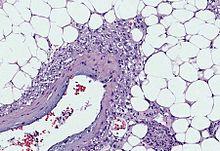

Myoid cells with clear cytoplasm spinning off of large vessels in a background of mature fat, the classic microscopic features of angiomyolipoma

Angiomyolipomas are tumours consisting of perivascular epithelioid cells (cells which are found surrounding blood vessels and which resemble epithelial cells). A tumour of this kind is known as a PEComa, from the initials of perivascular epithelioid cell. Older literature may classify them as hamartomas (benign tumours consisting of cells in their correct location, but forming a disorganised mass) or choristoma (benign tumours consisting of normal cells in the wrong location). PEComas are themselves a kind of mesenchymal tumour which involves cells that form the connective tissue, cardiovascular, and lymphatic systems.[3]

An angiomyolipoma is composed of varying proportions of vascular cells, immature smooth muscle cells, and fat cells.[3] These three components respectively give rise to the components of the name: angio-, myo-, and lip-. The -oma suffix indicates a tumour.